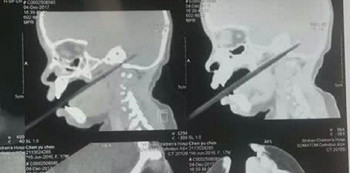

She was rushed to the hospital where doctors ran a CT scan on her. They then arranged for her to undergo surgery immediately, and found that 2cm of the chopstick had punctured her cerebellum (the part of the brain responsible for motor movement).

chopstick pierce toddler brain

PHOTO: Sin Chew Daily/Asia News Network

The chopstick had also pierced through her internal jugular vein. To make things worse, there were even rice grains on the chopstick.

Fortunately, it missed her brainstem, which would have killed the girl. Chenchen is now undergoing treatment in the intensive care unit as she still runs the risk of intracranial infection.